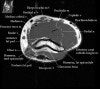

1. Coronal section

1) Collateral ligament

2) Common extensor/flexor tendon group patholgy as well as epicondylitis